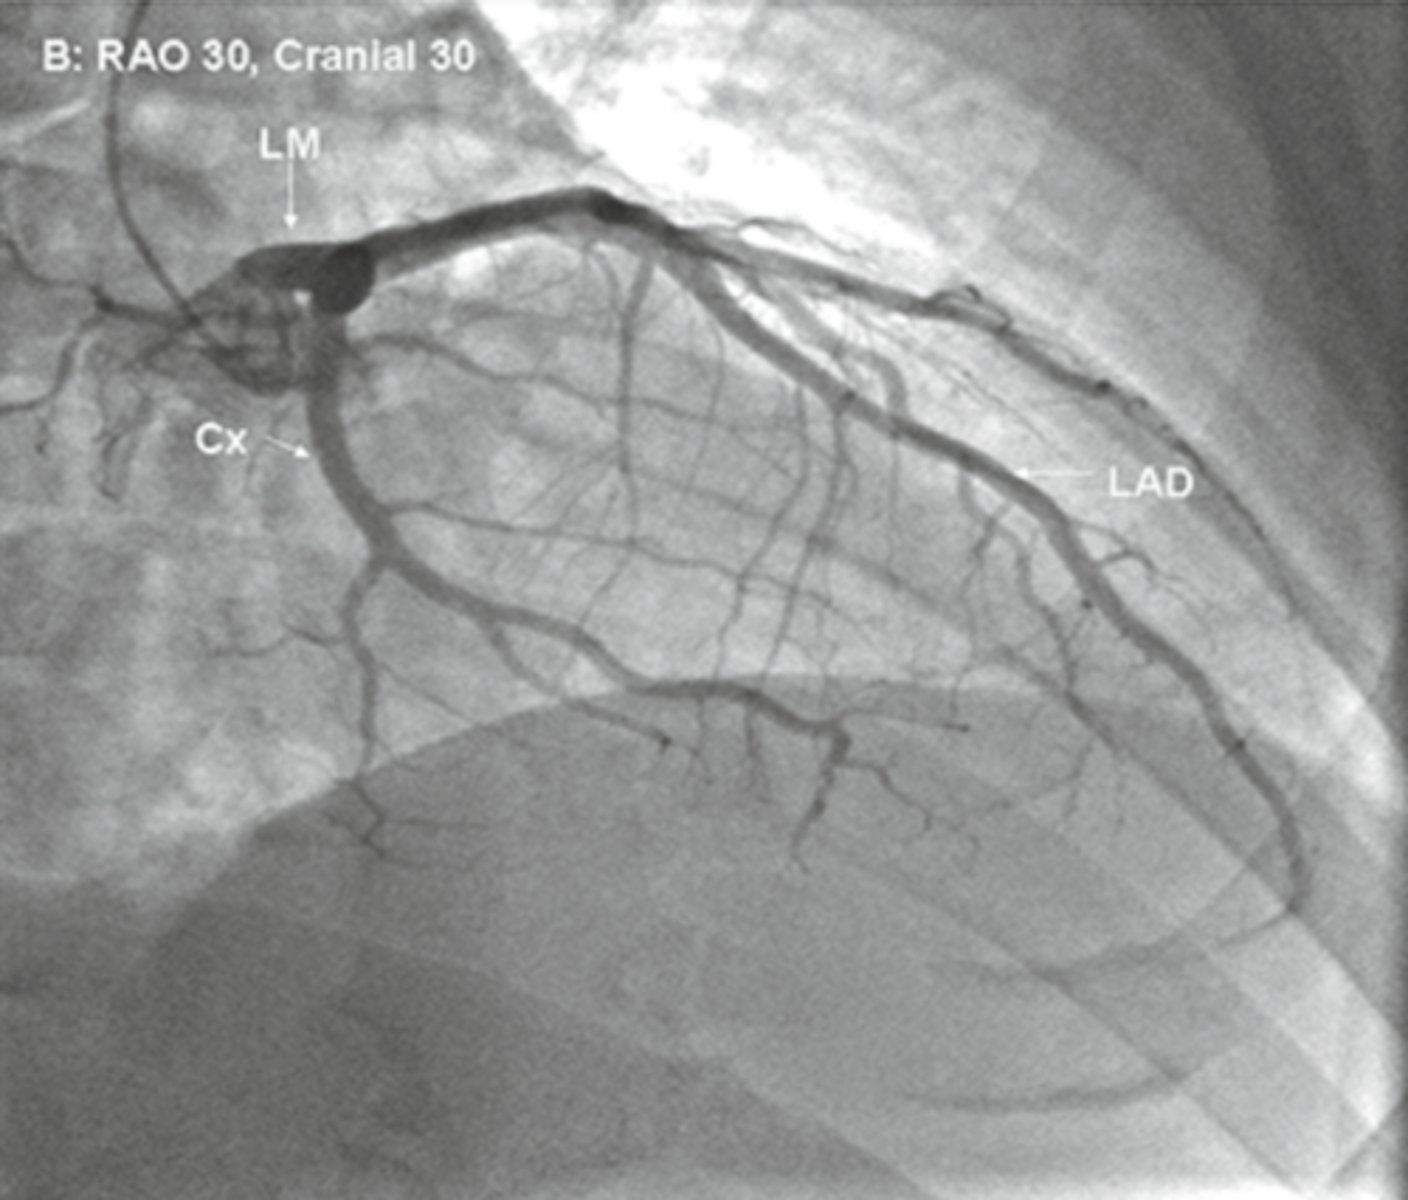

RAO

Cx is in front, what view

LAO

LAD is in front, what view

rao cranial

view

rao caudal

lao cranial

lao caudal

LAD

in LAO caudal what vessel is on top